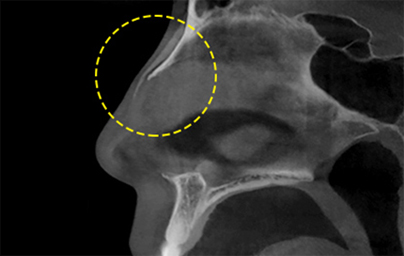

透過立體的骨骼圖進行精準診斷的 3D CT